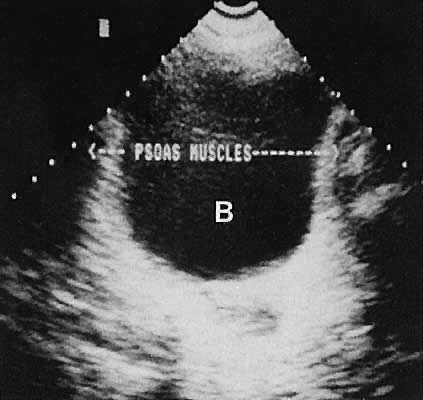

On either side of the urinary bladder in the anterolateral pelvic area are the iliopsoas muscles. These areas should not be confused with pathologic pelvic masses (Fig. 4).

Fig. 4. Normal psoas muscles, transverse plane, transabdominal scan. B, bladder.